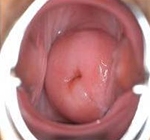

宫颈糜烂是慢性宫颈炎的一种表现,主要是指在阴道内的子宫颈粘膜完全剥离,露出底部粗糙组织面,如溃疡样,无上皮覆盖。很多宫颈癌患者都是因为在患有宫颈糜烂的时候没有及时治疗导致的,很多人都认为宫颈糜烂是一种很正常的现象,以至于慢慢的病情发展的越来越严重了。

治疗前